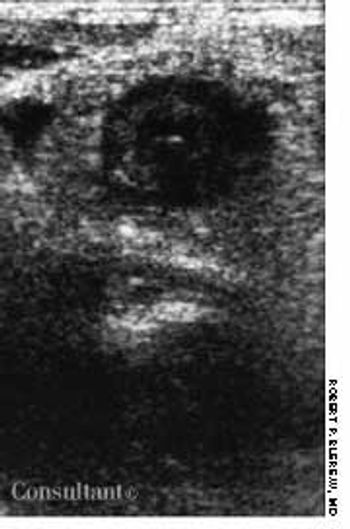

An 87-year-old man experienced a scratchy throat and difficulty speaking, which cleared after taking over-the-counter throat lozenges.